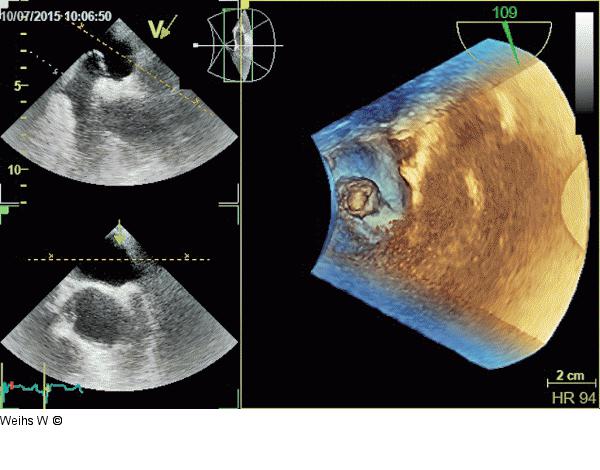

Abbildung 2: Vorhofseptumaneurysma 3D-Darstellung des Vorhofseptumaneurysmas (Blick vom linken Vorhof auf die Fossa ovalis). |

3D-Darstellung des Vorhofseptumaneurysmas (Blick vom linken Vorhof auf die Fossa ovalis). |